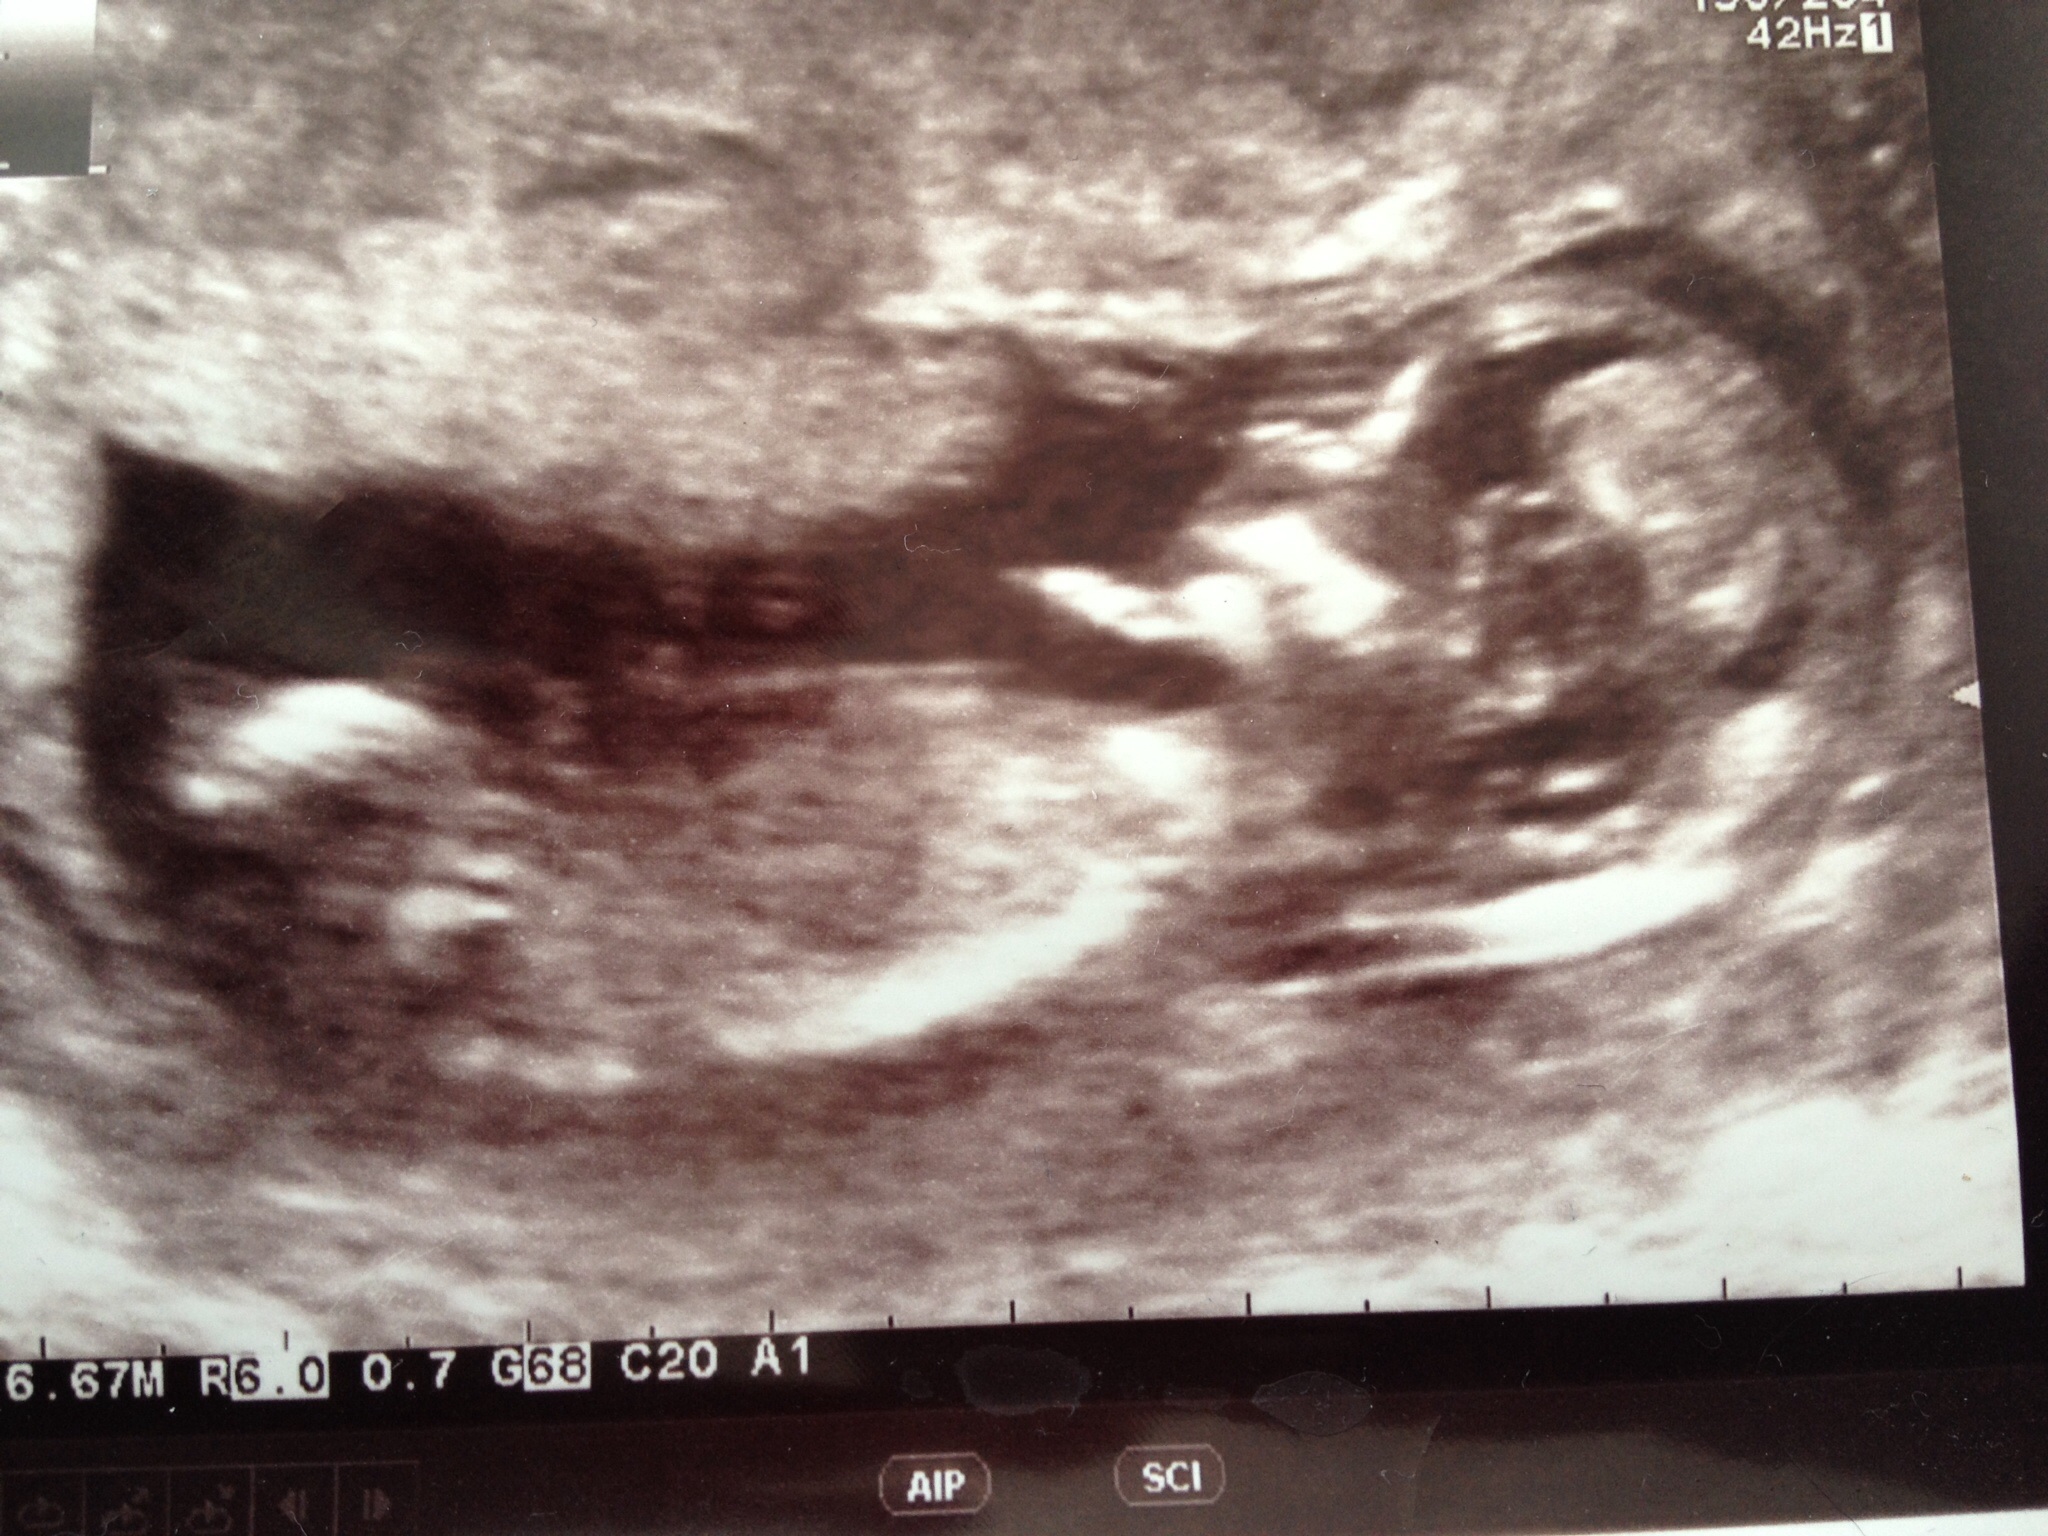

Does this 12+4w scan look girlie to you?x

Attachment 24989

Thank you xx